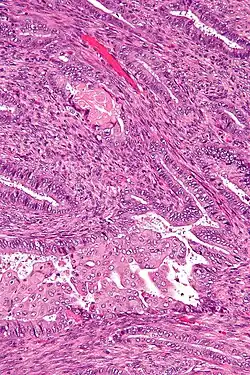

| Micrograph of an atypical polypoid adenomyoma. H&E stain. | |

APAs are characterized by glands with abnormal shapes that: (1) often have squamous metaplasia, and (2) are surrounded by benign smooth muscle.[1] Nuclear atypia, if present, is mild.

The microscopic differential diagnosis includes endometrial carcinoma and endocervical adenocarcinoma.